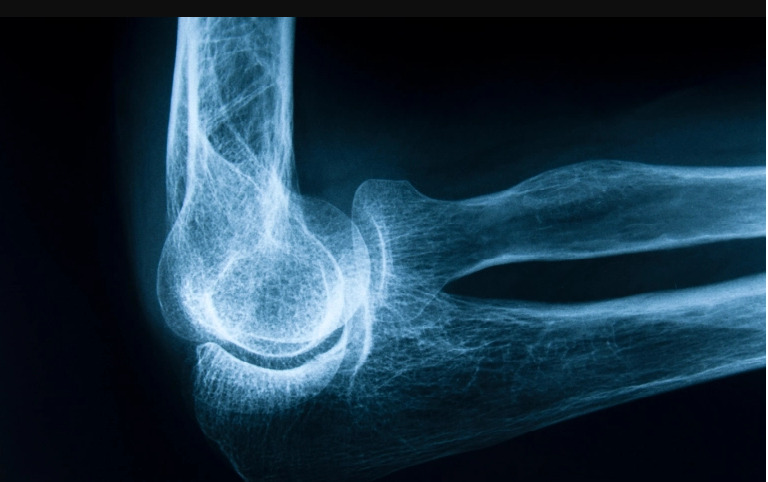

تمكن علماء روس من جامعة كورولوف وجامعة سمارا الطبية ومختبر "هندسة الأنسجة" الدولي من ابتكار مادة جديدة لتصحيح علاج هشاشة العظام- هيدروكسيباتيت /HAP/، باستخدام تقنية فريدة من نوعها حاصلة على براءة اختراع "ليوبلاست"، تسمح ليس فقط باستعادة مكونات النسيج العظمي المعدنية المفقودة، بل والعضوية أيضا.

وأفادت مجلة /جورنال أوبتيكال تكنولوجي/، بأن هشاشة العظام، مرض مزمن يصاحبه انخفاض كثافة المعادن تدريجيا في النسيج العظمي، ما يؤدي إلى هشاشة العظام وانكسارها، ووفقا للعلماء يحتل هذا المرض حاليا المرتبة الرابعة بعد أمراض القلب والأوعية الدموية والسرطان ومرض السكري.

وأشار العلماء إلى أنهم أجروا تجارب لدراسة تركيب النسيج العظمي عند الإصابة بالهشاشة وذلك لمعرفة التغيرات الحاصلة في بنية النسيج في أنواع مختلفة من هشاشة العظام بدءا من المرحلة الأولية وانتهاء بالمرحلة الثانوية.

وقالت يلينا تيمتشينكو، الأستاذ المساعد في جامعة /سمارا/، "تحتوي الهيدروكسيباتيت المستخدمة حاليا على مكونات معدنية فقط، وأما المادة الجديدة فتركيبها يحتوي على مكونات معدنية وعضوية، ما يسمح باستعادة مواد النسيج العظمي المعدنية المفقودة لتصحيح علاج هشاشة العظام والمواد العضوية التي تعتبر إطارا لجميع الأنسجة العضوية"، مضيفة أن التحاليل التي أجريت أظهرت أن هذه المادة الجديدة لا مثيل لها في العالم حاليا.

وأضافت "هشاشة العظام الأولية، هي عندما لا تعرف أسباب تطور المرض، أما الثانوية فتظهر عند إصابة الجسم بأمراض معينة، وقد أخذ العلماء هذه الأمور في الاعتبار وحددوا معايير فردية لعلاج مرض الهشاشة، باستخدام /HAP/".